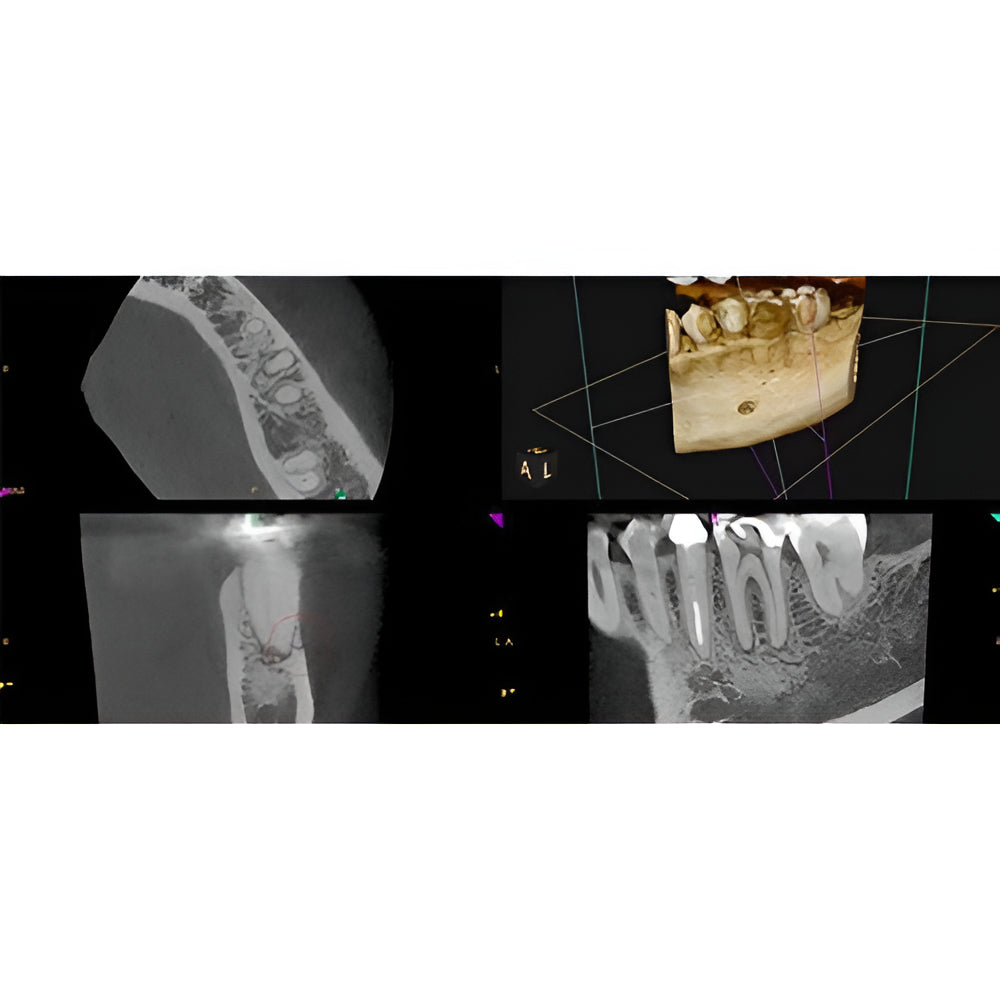

Enter a world of crystal-clear 3D images with the CS 8200 3D Access-a CBCT system that’s state-of-the-art, but intuitive and easy to use, taking your dental practice to the next level. Enjoy CBCT imaging that’s easier than you think and built on an open platform so that you can activate your future practice here and now.

- Versatile 4-in-1 solution ideal to expand treatment options

- Built on an open platform for a seamless workflow